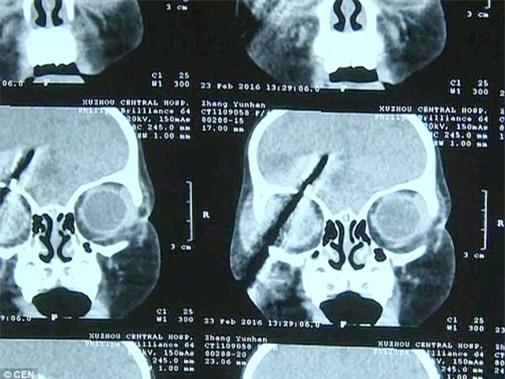

Ngay lập tức, gia đình đã nhanh chóng đưa cô bé đến bệnh viện Trung ương Từ Châu trong tình trạng nguy kịch. Tại đây, các bác sĩ đã thực hiện chụp X-quang và quét CAT để xem mức độ nghiêm trọng của vết thương. Kết quả kiểm tra cho thấy, phần đinh tua vít đâm vào đầu cô bé có độ dài khoảng gần 8 cm nhưng rất may nó đã đi lệch một góc cách mạch máu lớn chỉ vài mm.

Hình ảnh phim X quang cho thấy chiếc tua vít phát hiện phần tua vít đâm vào má phải xuyên qua mắt lên não bộ.

Tiến sĩ Giang Đức Hoa, bác sĩ trực tiếp thực hiện ca phẫu thuật loại bỏ tua vít đâm xuyên đầu bé gái cho biết: “Chúng tôi đã tiến hành chụp X-quang và phát hiện phần tua vít đâm vào má phải xuyên qua mắt lên não bộ cháu bé dài khoảng gần 8cm và chỉ một vài mm nữa nó sẽ lấy đi mạng sống của cháu bé. Tuy nhiên, cháu bé cần phải thực hiện một cuộc phẫu thuật khẩn cấp để loại bỏ tua vít”.